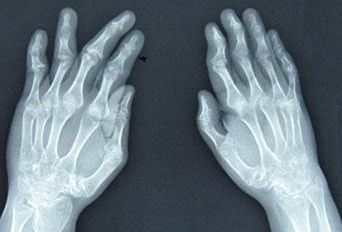

郑州主治类风湿医院介绍到类风湿关节炎是一种自身免疫性疾病,主要侵犯全身所有能动的关节…[详情]

RA ①晚期 ②并发症 病史:8年+

疗后患者双膝下蹲自由,上下台阶无压力,双腕关节、双手掌指关节疼痛消失,双手指恢复关节功能,整个人面色恢复,身体各项机能均提升。